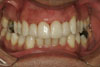

Gallery Our Clinic Before & After Photos Case Presentation Veneers Events & Awards BACD MEETING LONDON Investor in People Award Ceremony 2001 Dr Bill Dorfman the founder of Zoom tooth whitening and Dr Voghoui British Dental Association Good Practice Award Ceremony London 2008 Mr Gordon Watkins, president of the B.D.A, Dr Voghoui and his team.